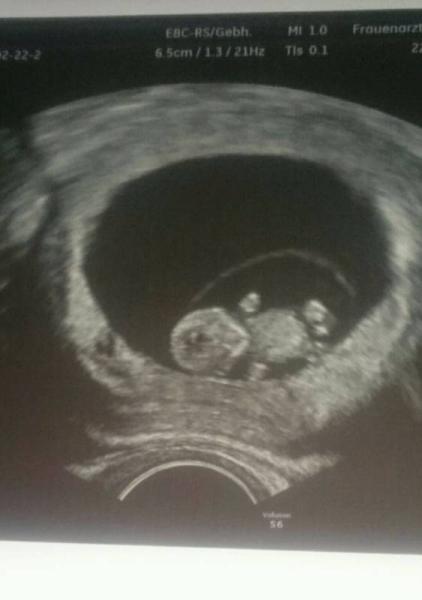

Das war 9+2 bei mir